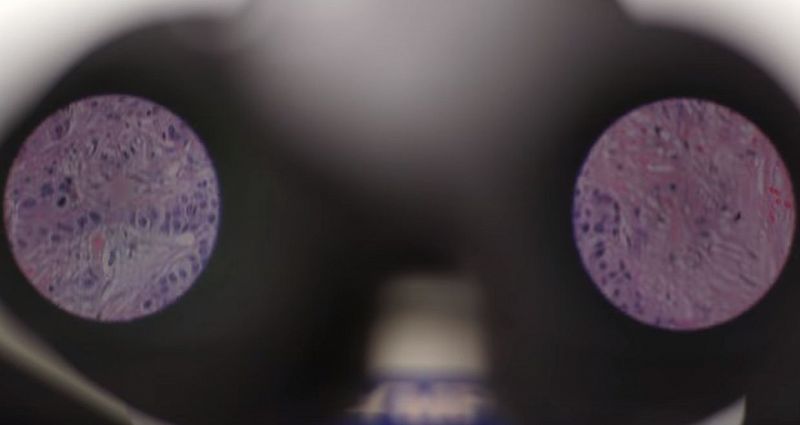

Разработчики Google на ежегодной конференции AACR представили прототип "умного микроскопа", который позволяет обнаружить раковые клетки, сообщается в блоге Google Research.

Как отметили специалисты, компьютер может в режиме реального времени анализировать изображение с камеры и пометить области, похожие на злокачественные образования. Это делается при помощи встроенного в него экрана дополненной реальности. Специалисты корпорации отметили, что за основу для подобной разработки можно взять обычный прибор, который применяют в больницах и исследовательских центрах.

Специалисты также подчеркнули, что им было необходимо интегрировать экран дополнительной реальности в оптику и сформировать глубокую нейронную сеть. Эксперты корпорации сконцентрировали своё внимание на метастазах рака молочной железы в сигнальных лимфоузлах и раке предстательной железы.